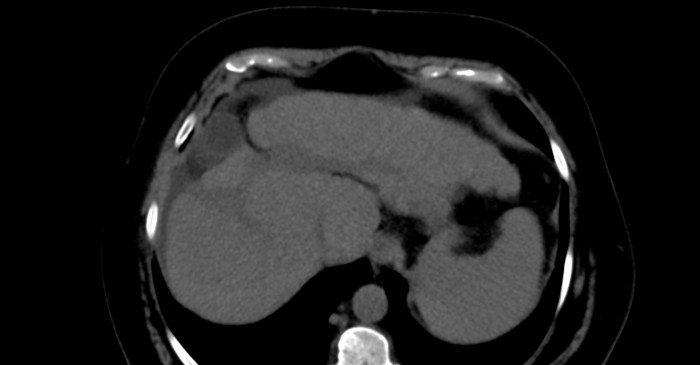

Presentamos el caso de un paciente con diagnóstico de cáncer de mama derecha triple negativo, para el cual se solicita estudio de extensión para estadificación. Se realizó tomografía (TC) de tórax y abdomen simple identificando la vesícula biliar de situación suprahepática (Figs. 1 y 2) asociado a hipoplasia del lóbulo derecho (Fig. 3), así como escaso líquido perivesicular (Fig. 4); no hay lesiones hepáticas que sugieran actividad metastásica. En el resto del estudio no se identificaron alteraciones, ni variantes anatómicas.

Figura 2

TC de abdomen simple en corte axial. Se observa la vesícula biliar ectópica asociada a escaso líquido libre perihepático.